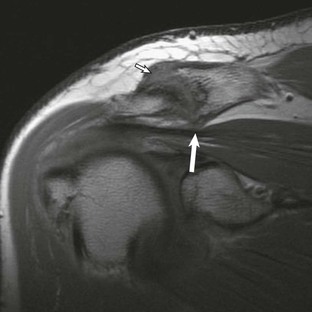

Anterior and lateral downward sloping of the anterior acromion can also narrow the supraspinatus outlet and potentially result in impingement.80,81 Anterior downward sloping (see Fig. 44-11, B) is demonstrated on oblique sagittal MRI; lateral downward sloping (see Fig. 44-11, C) is best seen on the oblique coronal images. An enthesophyte (Fig. 44-12) extending off the anteroinferior aspect of the acromion can also be clearly demonstrated on MRI. It typically appears as a marrow-containing osseous excrescence, which should have MRI signal characteristics similar to those of the adjacent acromion marrow (bright on T1-weighted images). Potential pitfalls include the attachment of the coracoacromial ligament and the deltoid tendon insertion (see Fig. 44-11, A and C) on the anterior acromion. These structures may mimic an osseous excrescence, but they can be differentiated from enthesophytes because they lack marrow signal and appear dark on all pulse sequences. The acromion should also be evaluated for os acromiale (Fig. 44-13), which is an accessory ossification center along the outer edge of the anterior acromion. It is normally fused by 25 years of age. An association exists between persistent os acromiale and impingement of the rotator cuff.82-86 The deltoid muscle attaches to the inferior aspect of the accessory ossicle, and contraction of the deltoid results in a downward motion of the unstable segment, potentially leading to impingement of the underlying rotator cuff. Os acromiale is demonstrated best on axial images (see Fig. 44-7, A), but it can also be seen on oblique sagittal or oblique coronal images (see Fig. 44-7, B),85 on which it should not be confused with the adjacent AC joint. MRI signs of instability of the os acromiale include fluid signal within the synchondrosis or sclerosis, cystic change, or marrow edema on either side of the synchondrosis (Box 44-2).

Hypertrophic changes of the capsule and inferiorly directed osteophyte formation of the AC joint (see Fig. 44-13) can also be associated with impingement.64 MRI demonstrates these changes, as well as associated mass effect on the underlying rotator cuff. The coracoacromial ligament (Fig. 44-14) is a soft tissue structure that forms part of the coracoacromial arch. It extends from the coracoid to the acromion and is well seen on oblique sagittal MRI. It normally measures less than 2 mm in thickness and extends across the rotator interval and anterior aspect of the supraspinatus tendon. The role of the coracoacromial ligament in impingement remains controversial; some persons believe that thickening or ossification (see Fig. 44-14, B) of the ligament may be a potential cause of impingement, whereas others believe that thickening results from impingement.87,88